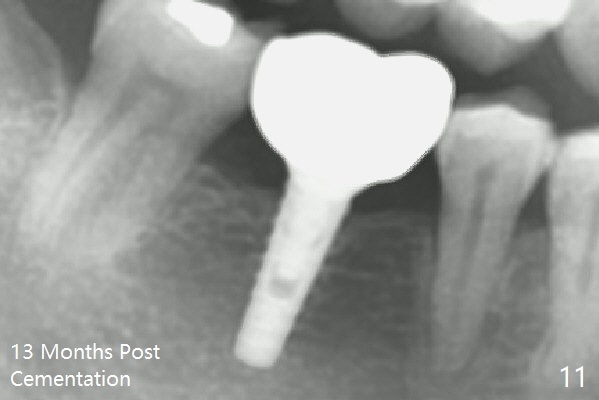

A provisional is fabricated 1 month postop to prevent the tooth #31 from rotation under the tension of the open coil spring, as mentioned above. Acrylic is added distal for #31 distalization nearly 2 months postop. More definitive orthodontic action begins 3 months postop (Fig.7, banding and open coil spring). The edentulous space increases to satisfactory width 3.5 months postop (Fig.8). A normal sized crown is delivered 4 months postop (Fig.9). The patient is pleased with the new tooth (Fig.10 nearly 6 months post cementation). There is no bone loss 13 months post cementation (Fig.11 (pan), 12 (CT coronal section (L: lingual))).